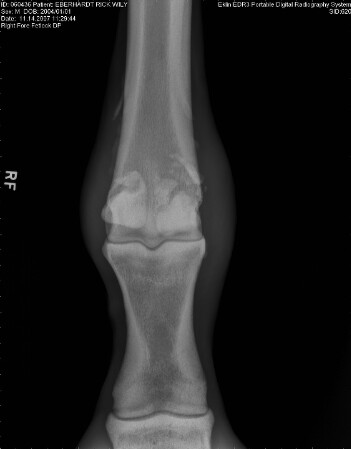

• “Wily” Eberhart, 3 y/o Quarterhorse gelding presented with a three week history of lameness on the right front forelimb. There is a firm swelling present at the fetlock joint of the right forelimb. The horse was stall rested and given 1 gram of phenylbutazone daily for a three week duration.

• On presentation, there was a high suspicion of a proximal sesamoidian fracture therefore radiographs were taken immediately.

Figure 2 - Dorsal Palmer view